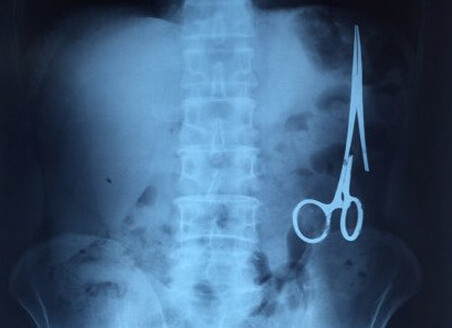

剪刀留腹中18年:X光顯示遺留在病人腹中的剪刀

剪刀留腹中18年:2016年1月2日,越南青年報報道一起醫療事故,越南鑄鋼醫院的醫生從54歲患者M.V.N腹中取出一把醫用剪刀。這把剪刀是很久前患者手術時遺留的,剪刀留在患者腹中已有18年。

醫務人員從X光片中看到,在病人腹部左側有一把剪刀,與結腸緊挨著。剪刀的把手已經生銹并且有一個把手已經爛斷了,患者的部分器官已經與剪刀粘連起來。

ct檢查顯示,M.V.N的腸子中有一把醫用剪刀。M.V.N證實,他曾于1998年6月份在北江省綜合醫院接受手術,在此后18年來從未進行過任何手術。近來,他感到腹部有些疼痛,并試圖通過服用藥物治療。